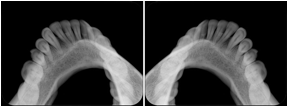

- OO-1. Intra-oral Full Mouth Series Structured Display